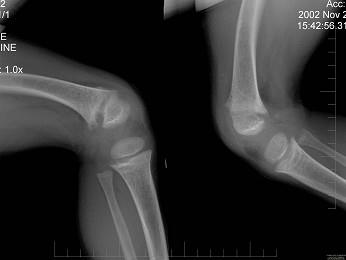

问题 男,6岁,睡眠差,夜惊,多汗;出牙较迟;血清磷减低、血清钙减低、碱性磷酸酶升高卜,请结合图像选择最佳选项 ( )

选项 A、肾性维生素D缺乏病 B、脆骨病 C、骨软化症 D、先天性骨梅毒 E、维生素D缺乏病

答案 E